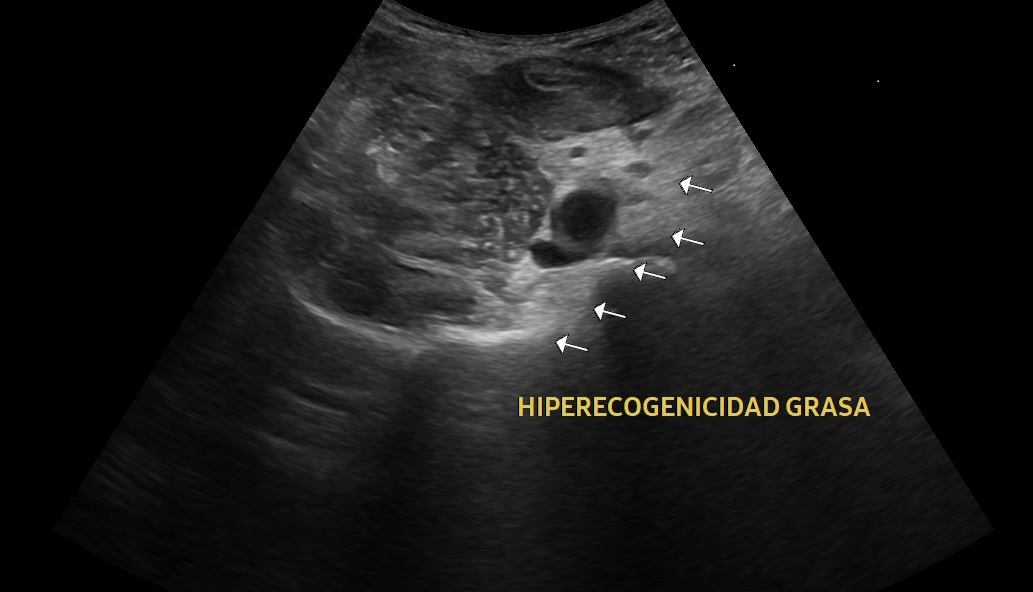

Se realiza una exploración abdominal ecográfica donde se observa hígado de ecogenicidad normal sin lesiones ocupantes de espacio. Vesícula biliar normal, vía biliar no dilatada. Ambos riñones de tamaño y aspecto normales. Páncreas, bazo y aorta normales. En fosa ilíaca derecha se observa apéndice cecal engrosado (imagen 1) con llamativa hiperecogenicidad de la grasa abdominal en relación con cambios inflamatorios (imagen 2). Colección abdominal en relación con cambios inflamatorios 3 x 3 x 5,3 cm (imagen 3).

La ecografía clínica se ha convertido en una herramienta útil para el diagnóstico temprano de apendicitis aguda. Gracias a su accesibilidad, permite realizar una evaluación rápida, ayudando a identificar signos como el engrosamiento del apéndice o la acumulación de líquido periapendicular.